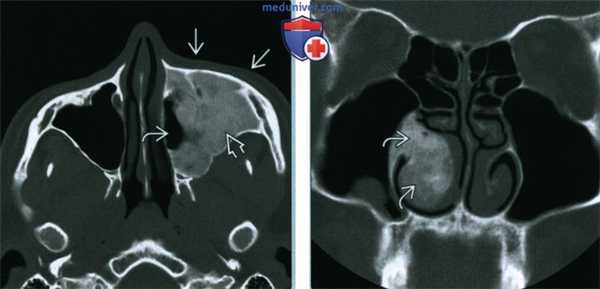

(Слева) На корональной КТ в костном окне определяется ПФД с поражением глазницы, петушиного гребня, решетчатого лабиринта, средней носовой раковины справа. Оцените типичную картину «матового стекла». Носовая перегородка смещена влево.

(Справа) На аксиальной МРТ (Т2ВИ) у этого же пациента определяется выраженный гипоинтенсивный сигнал в пораженных костях. Поражение однородное и сопоставимо с «матовым стеклом» на КТ. При большем количестве фиброзной ткани ожидаемы очаги с более интенсивным сигналом и более длительным временем повторения.